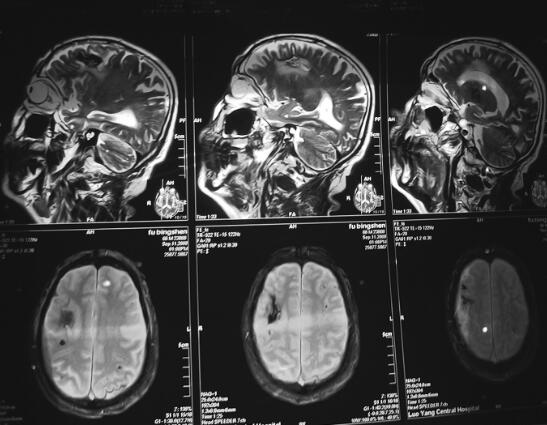

转归及预后:患者随访2年,目前一般状况良好,反应稍差,可从事日常活动。治疗8个月后复查MRI见图4。

图4 2009年9月治疗后复查脑磁共振图像